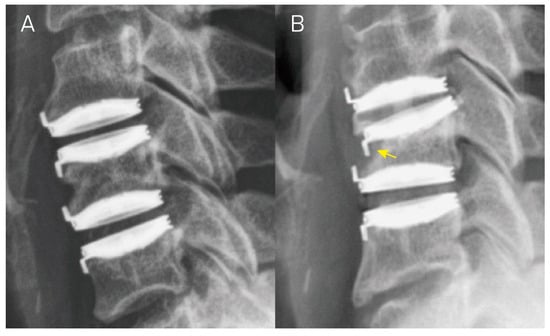

2.2. Radiographic Evaluation